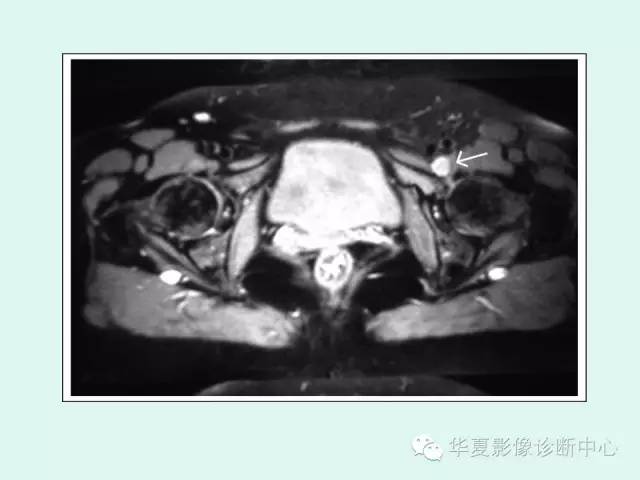

【PPT】大转子周围滑囊炎